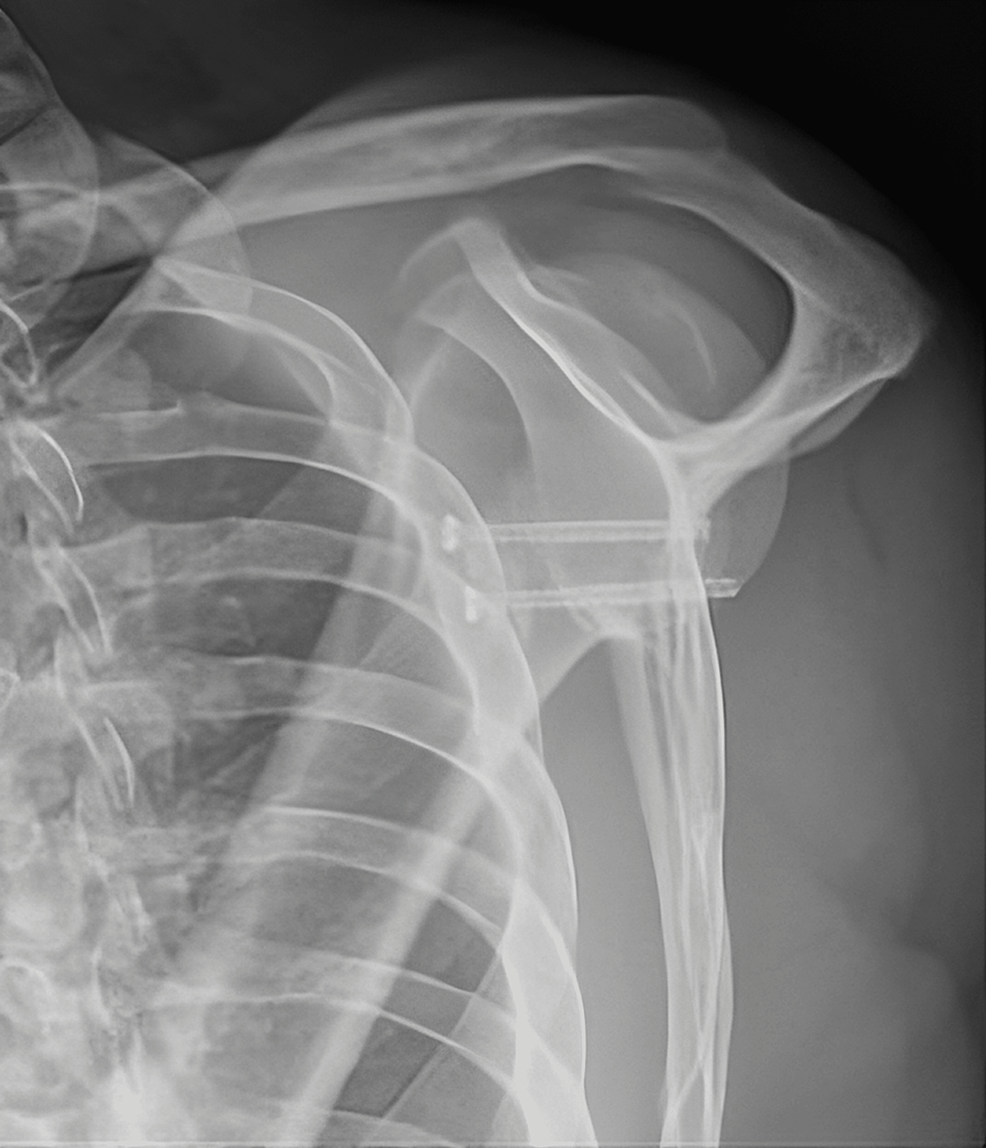

Early complications of the Latarjet procedure Image Open Latarjet Procedure Cpt (2) osteotomy and subsequent release; six key stages include: Dissect the interval between the deltoid and the. (1) coracoid exposure and initial release; latarjet procedure is commonly performed for recurrent anterior shoulder instability with glenoid side bone. in this procedure, the provider repairs a tear in the shoulder joint capsule and tightens the joint capsule in the. Open Latarjet Procedure Cpt.